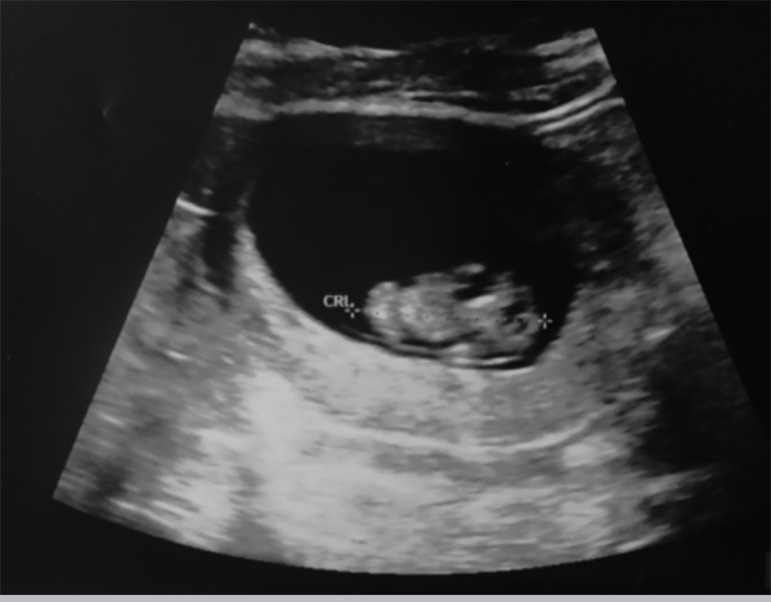

在本报告中,我们提出了一个不寻常的案例,一对夫妇通过ICSI成功怀孕,并收集了单个卵母细胞。卵母细胞复合体(COC)在触发后36.5小时被检索,发现处于II中期,在触发后约39小时进行精子注射。注射后18小时,单个卵母细胞受精,第2天发育为4细胞级胚胎,第3天发育为8细胞级胚胎,并将其放置在子宫腔中。妊娠结果为β-hCG阳性。在七周时进行的扫描显示,存在一个羊膜囊和胎儿心跳。正在进行的妊娠在妊娠24周时平安无事。

In this report, we present an unusual case of a couple who achieved a successful pregnancy by ICSI with a single oocyte collected. The cumulus-oocyte-complex (COC) was retrieved at 36.5 hours post trigger, and was found to be at metaphase II, when sperm injection was performed at around 39 hours post trigger. At 18 hours post injection, the single oocyte was fertilized, developed to four-cell embryo on day 2, and 8-cell grade on day 3, when it was relocated in the uterine cavity. The pregnancy yielded a positive β-hCG result. The scan performed at seven weeks, revealed the presence of one amniotic sac with a fetal heartbeat. The ongoing pregnancy has been eventless at 24 weeks of gestation.